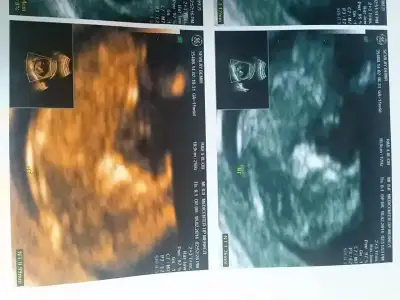

dr soylemeden siz gorun genital nub teorisi ( bebegin cinsiyeti)

Nubu buyuk erkek buyuzden bence ama emin degilim

Kizlar benim ufakligada bi bakarmisiniz doktor %90 erkek dedi ama birde siz bakin.

Arkadaslar bunada bi bakarmisiniz

Dr yuksek bi ihtimal vermis bnce kesin erkktr bu goruntu 4boyutlu nub gorunmez ama bakinca bacsk arasinda pipi gorunuoArkadaslar bunada bi bakarmisiniz

Dr yuksek bi ihtimal vermis bnce kesin erkktr bu goruntu 4boyutlu nub gorunmez ama bakinca bacsk arasinda pipi gorunuo

Siyah beyazida var ama orda sirti donuk bu fotodakide.pipimi degilmi.emin olamadim 14 haftalik suan.gerci bebek onden gidiyormus oyle iste :))) cok tesekkur ederim canimmm

Eki Görüntüle 992960 Eki Görüntüle 992961

Kizlar sanırım çözdüm, burada 11+6 günlüğüz, size zahmet bize de yoruuummmm lütfenn :))

Ben kiza bezettim cnm.tecrubeli degilim cok emin olma ama ben kiz diyorum.

Emin olamadim ama erkek olabilir hafatsi erken kesin erkkk diyebilcgmiz poz degil ama buna bnzeyen bi arkadasin oglu olcak suan kiz gibi goruntusu var ama

Başka bir doktor % 100 erkek demiş arkadaşıma kızlar % 85 kizken değişti durum Eki Görüntüle 994849

Teyzeleri benim miniğime de yorum yapar mısınız? 10+5 haftalık burda.

Eki Görüntüle 968281 Eki Görüntüle 968283

Iste bu resim. Benziyen resimler varsa kiyaslamakmicin